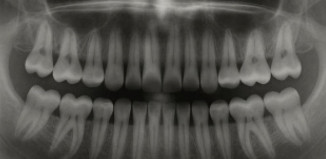

پشکنینا “رێژەیا شیرینیێ” د خوینێ دا یان پشکنینا نەخۆشییا شەکرێ

21/04/2026 00:46

4

هوزان عبدالرحمن أحمد گلۆکۆز (شەکرا خوینێ) بەربەلاڤترین جۆرێ شەکرێن سادەیە، سوتەمەنیا سەرەکییە بۆ خانەیێن زیندی د لەشێ مرۆڤی دا، گلۆکۆز ژێدەرێ وزەیێ یێ پەسەندکرییە بۆ...